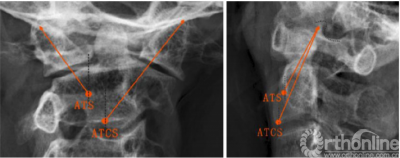

ATS和ATCS固定的轨迹可通过正、侧位X线片上的解剖标志来确定。在正位X线片中,螺钉轨迹朝向C1上关节突上外侧角,与侧块外侧缘间隙为2-3mm(图3,左)。然后测量α角,即ATS与ATSC螺钉相对于矢状面所形成的理想外展角。在侧位X线片中,ATS和ATCS固定方向均朝向C1上关节突后上角,并与上关节突后缘的间隙为2.3mm(图3,右)。此外,还测量了角β,即ATS与ATSC螺钉相对于冠状面所形成的理想倾斜角。将螺钉置入新鲜尸体标本后,在正、侧位X线片上分别测量ATS和ATCS的实际角α、β,以及ATCS和ATS的实际进钉点与C2椎体中线的横向距离。

图3正位和侧位x线片上ATS和ATCS的螺钉轨迹,(左)所有螺钉对准C1上关节突上外侧角;(右)所有螺钉对准C1上关节突上角(点附近);ATCS,前路经关节交叉螺钉;ATS,前路关节交叉螺钉

The ATS and ATCS trajectories were determined using the landmarks visible on anteroposterior and lateral x-rays. On the anteroposterior view, screw trajectories were aimed at the superolateral corner of C1 superior articular process, leaving 2–3 mm clearance from lateral margin of the lateral mass (Fig. 3, left). Then, the angle α, the ideal lateral angle of ATS and ATCS placement relative to the sagittal plane were measured. On the lateral view, the trajectories of ATS and ATCS were aimed at a point on the line between the superoposterior corner of C1 superior articular process and the superior end of the anterior arch, with 2–3 mm clearance from posterior margin of the superior articular process (Fig. 3, right). Moreover, the angle b, the ideal incline angle of the two screws placement relative to coronal plane were measured. After the screws were inserted into fresh cadaveric specimens, the actual angle a and b of ATS and ATCS were also measured on anteroposterior and lateral X-ray images, respectively, as well as the actual entry points of ATCS and ATS lateral from the midline of the C2 vertebrae.

Fig. 3 Trajectories of ATS and ATCS are shown on anteroposterior (left) and lateral radiographs (right). (left) All screws are aimed at the superolateral corner of C1 superior articular process; (right) All screws are aimed at the superoposterior corner of C1 superior articular process (around dot). ATCS anterior transarticular crossing screw, ATS anterior transarticular screw